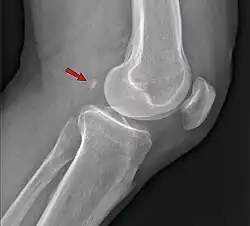

Fabela, no contexto da medicina, é um osso sesamoide situado na cabeça lateral do músculo gastrocnêmio nos membros inferiores, logo atrás da articulação do joelho.[1]

A fabela localiza-se no tendão da cabeça lateral do músculo gastrocnêmio e aparece circundada em seu aspecto anterior e posterior pelas fibras tendíneas nos estudos histológicos. Está ligado na maioria dos casos à cabeça da fíbula por um ligamento fabelo-fibular. Seu tamanho é variável, entre 4 e 13 mm.